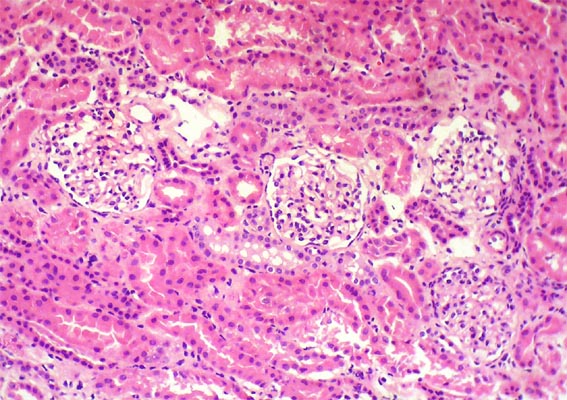

The patient is a 4-year-old girl who presented nephrotic syndrome in the first year of life, with biopsy in which focal segmental glomerulosclerosis was diagnosed. There was no response to multiple treatments. Molecular studies were unable to detect a specific genetic alteration. He developed ESRD at 3 years of age. She was in hemodialysis few months and was transplanted from a dead donor. Nephrectomy of a native kidney was done. Before the transplant, on dialysis, she had low urine output and non-nephrotic proteinuria without hypoalbuminemia or dyslipidemia. After transplantation presented progressive increase in proteinuria. Four post-transplant weeks there was complete nephrotic syndrome with proteinuria >100 mg/m2/h, dyslipidemia and hypoalbuminemia. Serum creatinine 0.5 mg/dL.

A renal biopsy was done, see the images.

Figure 1. H&E, X100.